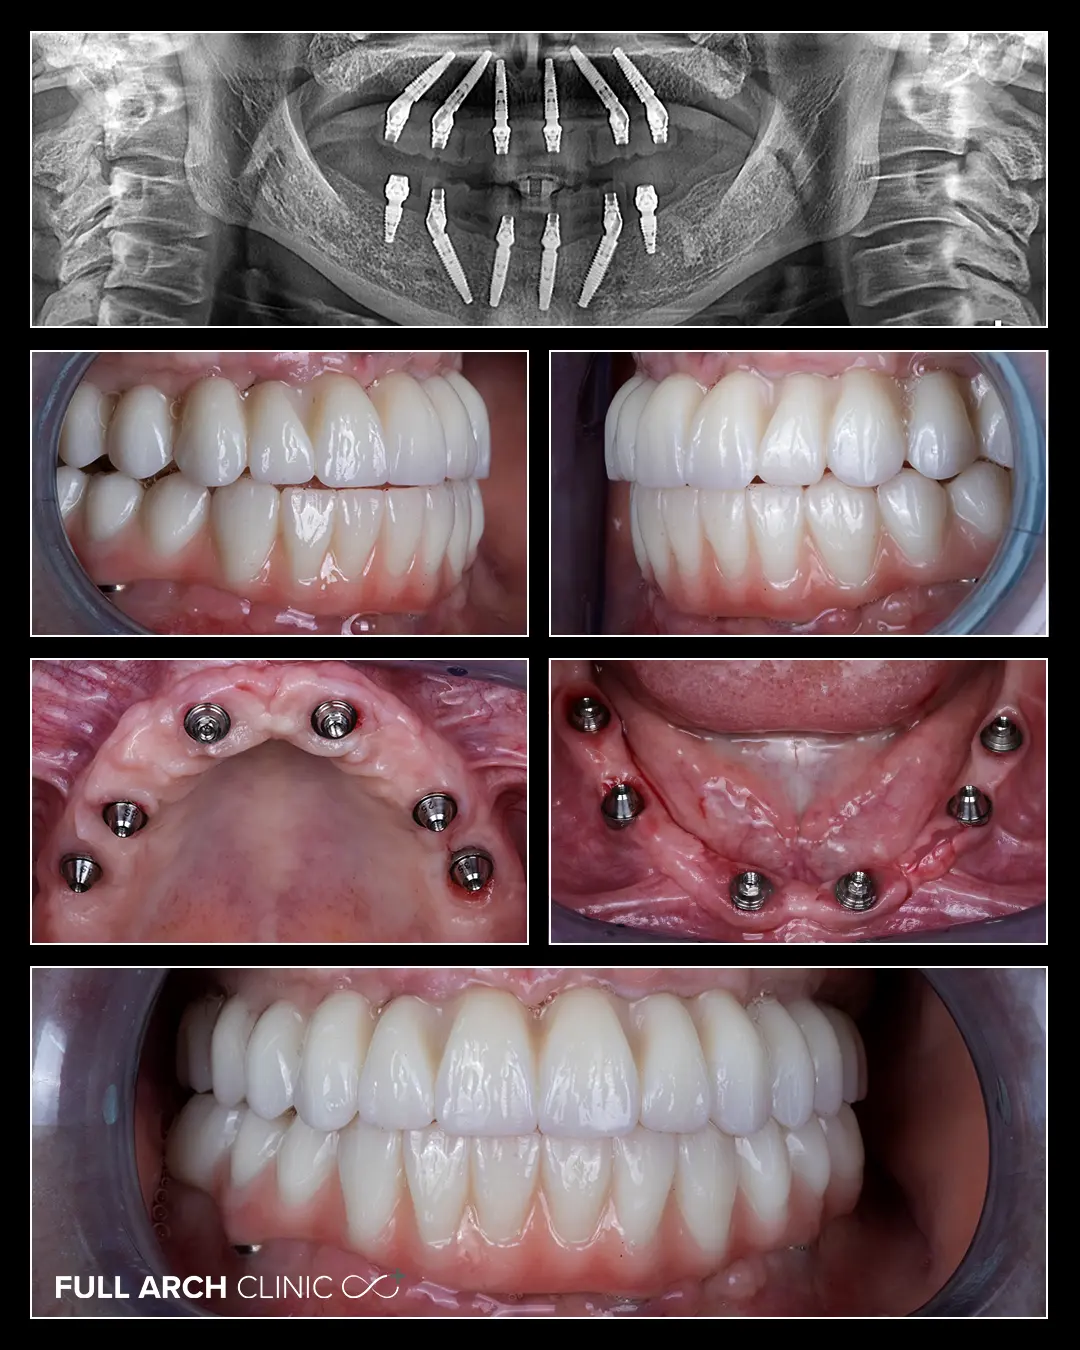

Doamna Oltean s-a prezentat la clinica noastra cu o proteza mobila partiala la maxilar si doua lucrari vechi mobile la mandibula.

Estetica generala si faptul ca nu putea sa manance cu aceste lucrari o afectau in fiecare zi.

In prima zi a tratamentului am realizat extractiile, curatarea infectiilor, si inserarea implanturilor la mandibula.

In a II-a zi a tratamentului am repetat acest proces pentru partea maxilara, iar in a III-a zi doamna Oltean a primit lucrarile provizorii pe care le lauda in video.

La 6 luni de zile am realizat si lucrari din zirconiu integral.

Dr. Andrei Stan - Implantologie

Dr. Daniel Bumbu - Protetica

Td. Darius Chindris - Design & Ceramica